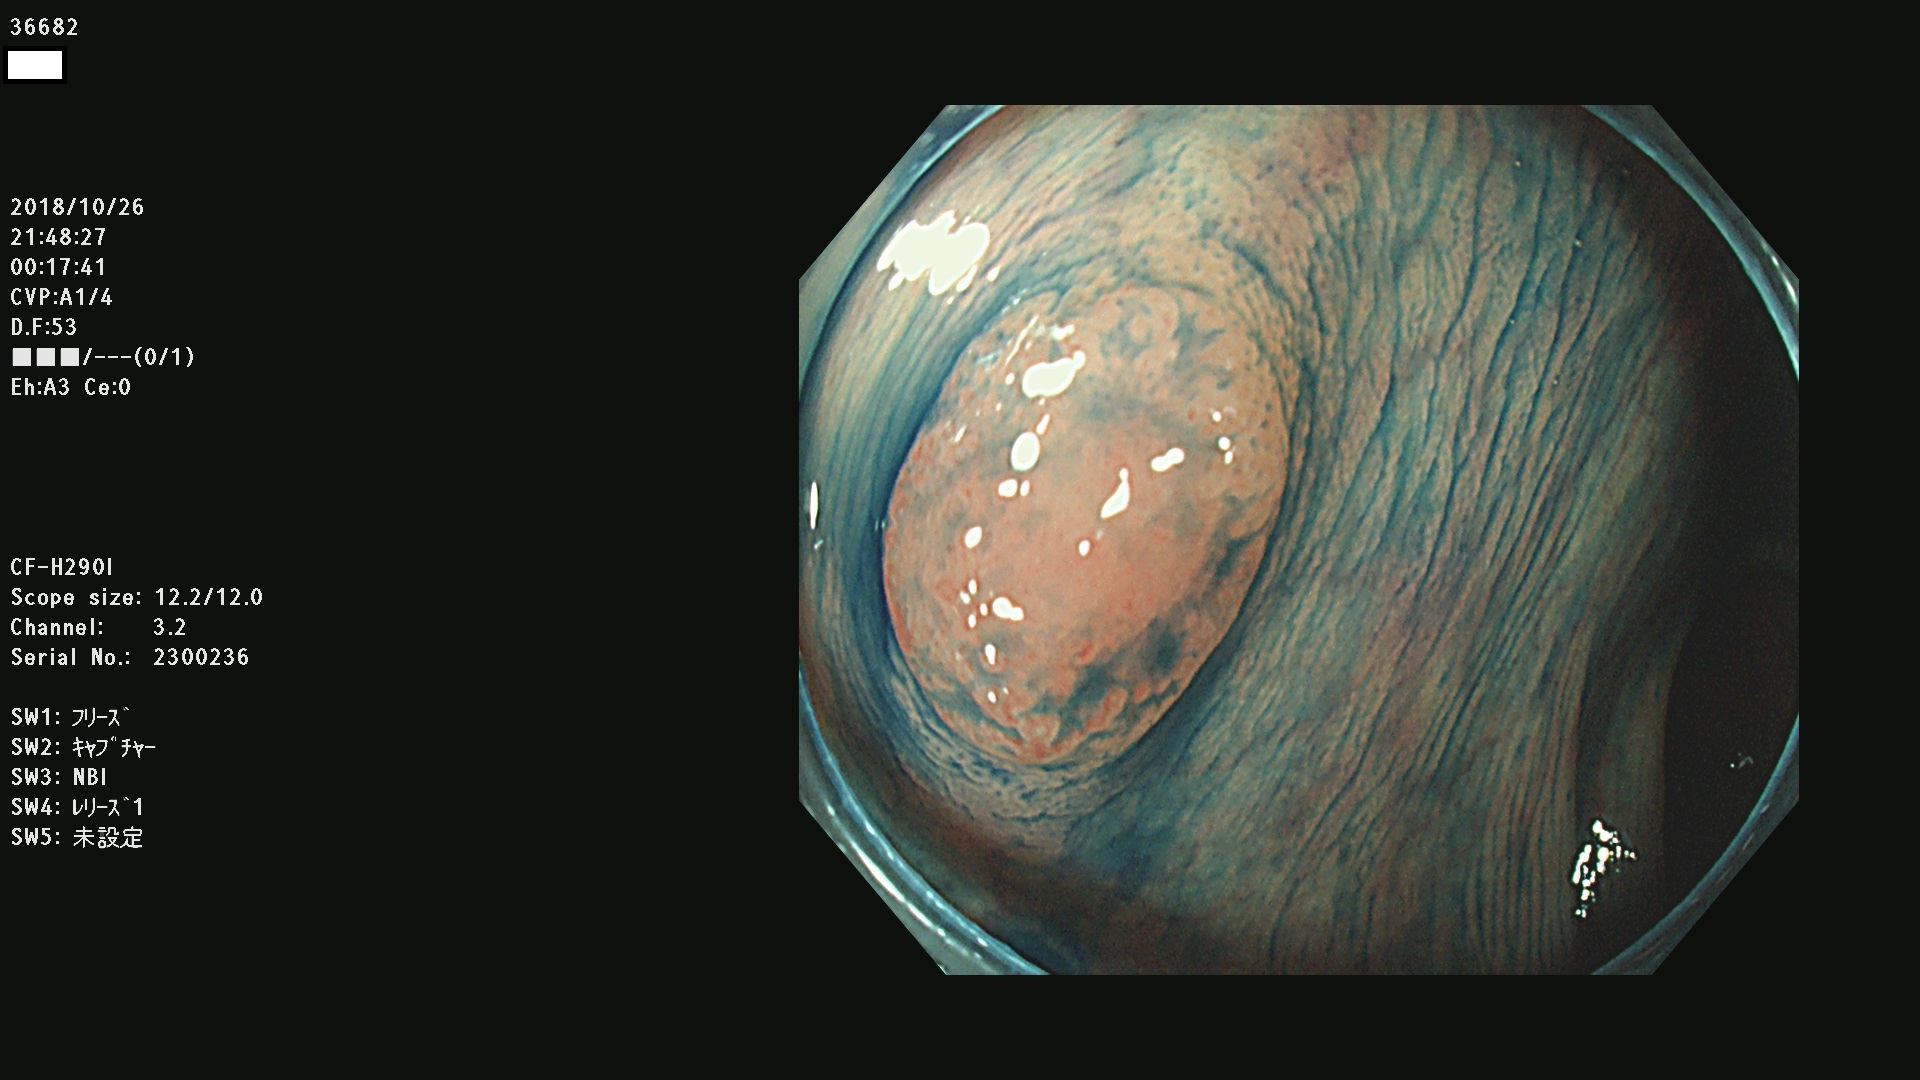

発見困難で危険性の高い平坦型病変(上記100名より抽出)

36600 36601 36603 36605 36606 36608 36609 36610 36611 36612 36613 36615 36617 36620 36621 36624 36625 36626 36627 36628 36629 36631(SSAPのみ) 36632 36633 36634 36636(SSAPのみ) 36637(SSAPのみ) 36639 36640 36642 36643 36644 36646 36647 36648 36649(SSAPのみ) 36650(SSAPのみ) 36652 36653 36654 36655(SSAPのみ) 36656 36657 36658 36659 36660 36661(SSAPのみ) 36665 36668 36669 36672 36673 36676 36677 36678 36679 36681 36682 36683 36684 36685 36687(SSAPのみ) 36691 36692 36693 36694 36695 36696 36697 36699(SSAPのみ)